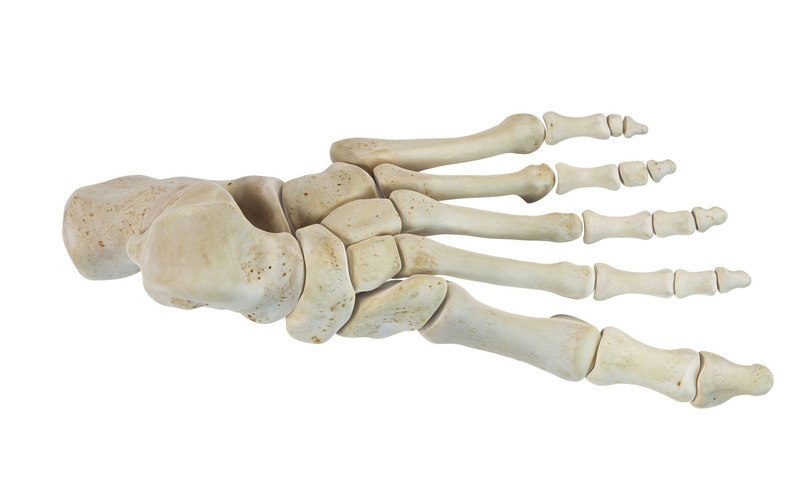

Các xương bàn chân

Các xương bàn chân bao gồm ba nhóm: Các xương cổ chân, các xương đốt bàn chân và các xương đốt ngón chân.

Các xương cổ chân: Gồm 7 xương, sắp xếp thành hai hàng:

• Hàng sau: Bao gồm xương sên và xương gót.

• Hàng trước: Bao gồm xương ghe, xương hộp, và ba xương chêm.

Các xương đốt bàn chân:

• Gồm 5 xương đốt bàn, đánh số từ trong ra ngoài: Xương đốt bàn I đến xương đốt bàn V.

• Mỗi xương có ba phần: Nền, thân và chỏm.

Một số đặc điểm giải phẫu xương chi dưới 3

Giải phẫu xương bàn chân với nhiều chi tiết nhỏ phức tạp

Các xương đốt ngón chân:

• Mỗi ngón chân có ba xương: Đốt ngón gần, đốt ngón giữa và đốt ngón xa.

• Ngoại trừ ngón chân cái (ngón I), chỉ có hai xương: Đốt ngón gần và đốt ngón xa.

• Mỗi xương có ba phần: Nền đốt ngón, thân đốt ngón và chỏm đốt ngón.